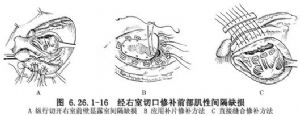

先經右房通過三尖瓣口初步探查和確定這類缺損部位和數目。於缺損相應部位做右室縱切口,切口距離冠狀動脈左前降支至少應在8mm以上。牽開右室切口,觀察缺損數目和大小(圖6.26.1-16A)。缺損較大,一般呈長條形,可應用長圓形補片修補。先繞肌緣預置一圈間斷褥式縫線,分別穿過補片緣,並一一結紮(圖6.26.1-16B)。若缺損窄長形,則可採用兩排聚四氟乙烯或滌綸墊片縫合,一排放在心內,另一排放在右心室前壁近室間隔部位,應用多個褥式縫合從心內穿過缺損後方肌肉緣,貫穿右心室前壁和心外的長條墊片,一般縫上3或4個褥式縫合,收緊縫線,結紮後即可將缺損牢固閉合(圖6.26.1-16C)。